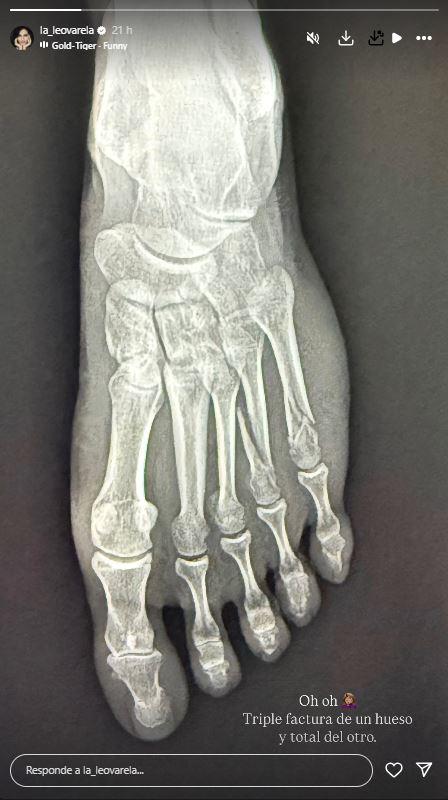

Unas horas después, la intérprete compartió una foto de una radiografía, donde dejaba en evidencia de las graves consecuencias que sufrió tras el accidente que protagonizó.

"Oh, oh. Triple fractura de un hueso y total del otro", escribió la actriz junto a la radiografía.